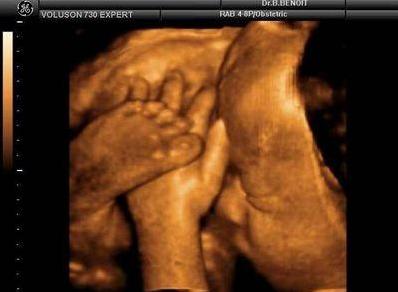

“四维彩超”——超声影像对于优生极其关键,可不少宝妈会遇到一种尴尬的情况,也让医生很头疼,那便是胎宝宝老趴着,基本上看不到五官及表情。

【在妇产科医院,你可以看到这样的胎宝】

霍霍,打拳啦~